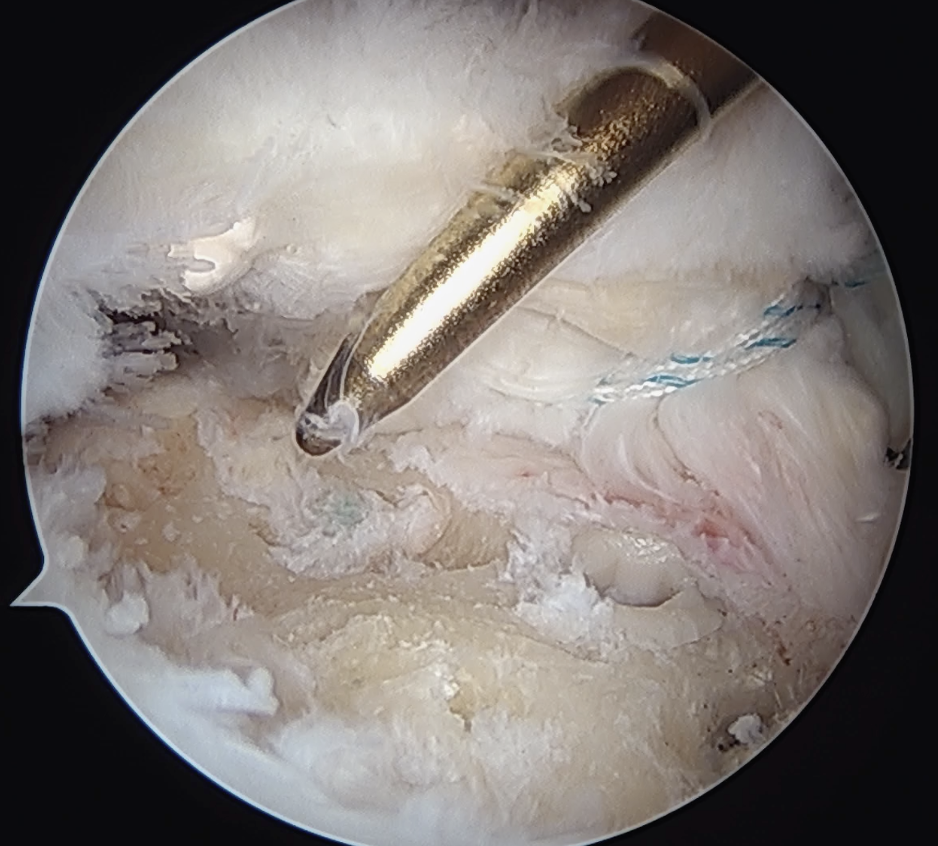

Medial row anchors

- inserted through additional stab incision for suture management

- just medial to articular cartilage

Pass sutures through medial cuff tendon

- camera posterior

- suture passer via lateral portal

- retrieve sutures through anterior portal

- repeat

- tie medial row